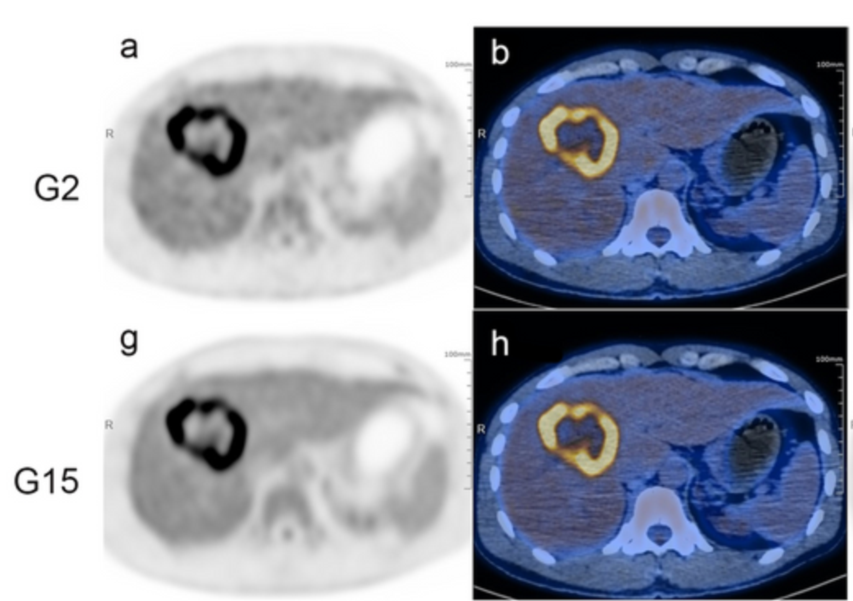

圖1:肝內膽管癌(ICC)受試者G2和G15的腹部橫斷位圖像對比

研究方法:研究納入了156名肝臟腫瘤患者,其中78名患者接受了uEXPLORER全身PET/CT檢查,采集時間為15分鐘,而后分別重建為2分鐘(G2組)和15分鐘(G15組)兩組圖像數據。作為對照組,另外78名患者接受了傳統PET/CT——uMI 780 PET/CT的檢查(G780組)。在定量指標評估方面,本文測算了每位患者最大腫瘤病灶的SUVmax、正常肝臟組織SUVmean和腫瘤-肝臟本底比值(腫瘤SUVmax與肝臟正常組織SUVmean的比值,TLR)。在病變可探查性分析中,以G15組作為參考,評估2分鐘采集時間的數據(G2組)在視覺評估方面以及病灶SUVmax、TLR等半定量參數方面的診斷性能;對G2組數據的肝臟病灶SUVmax和TLR進行了接受者操作特性曲線(ROC曲線分析);同時,所有這些患者手術標本的病理結果作會為對比的診斷金標準。

研究結果:對于所有患者,G2能夠顯示出G15中發現的病灶。G2中遺漏3個在G15組中顯示出的具有較低18F-FDG代謝的淋巴結,不過在最終的TNM分期方面,G2、G15和G780之間都沒有明顯差異。在異常代謝中,無論是良性病變還是惡性病變,G2和G15的肝臟SUVmean都高于G780(P<0.05);G2的腫瘤SUVmax和TLR都與G15和G780的相當。ROC曲線分析(SUV截斷點:4.34,TLR截斷點:1.34)表明,G2在檢測肝癌方面也有良好的敏感性。

研究結果表明,對于肝癌患者,由于全身PET/CT超長的軸距和超高的靈敏度,在2分鐘短時間采集條件下(G2組)的診斷性能與采集15分鐘的圖像相當,與傳統PET/CT全身檢查也有相似的診斷效能。過去通過傳統PET/CT,一次全身腫瘤檢查通常需要15~20分鐘的采集時間,如今借助全身PET/CT uEXPLORER這樣新技術有望直接縮短至2分鐘,更短的檢查時間能使科室診斷流程更加流暢,大幅提升患者的就診體驗。更重要的是,對于癲癇患者、難以耐受劇痛的腫瘤患者等人群而言,過去由于難以長時間保持靜止不動,無法正常進行PET/CT檢查,如今借助全身PET/CT進行短時間快速采集,讓這部分患者也能從中受益。